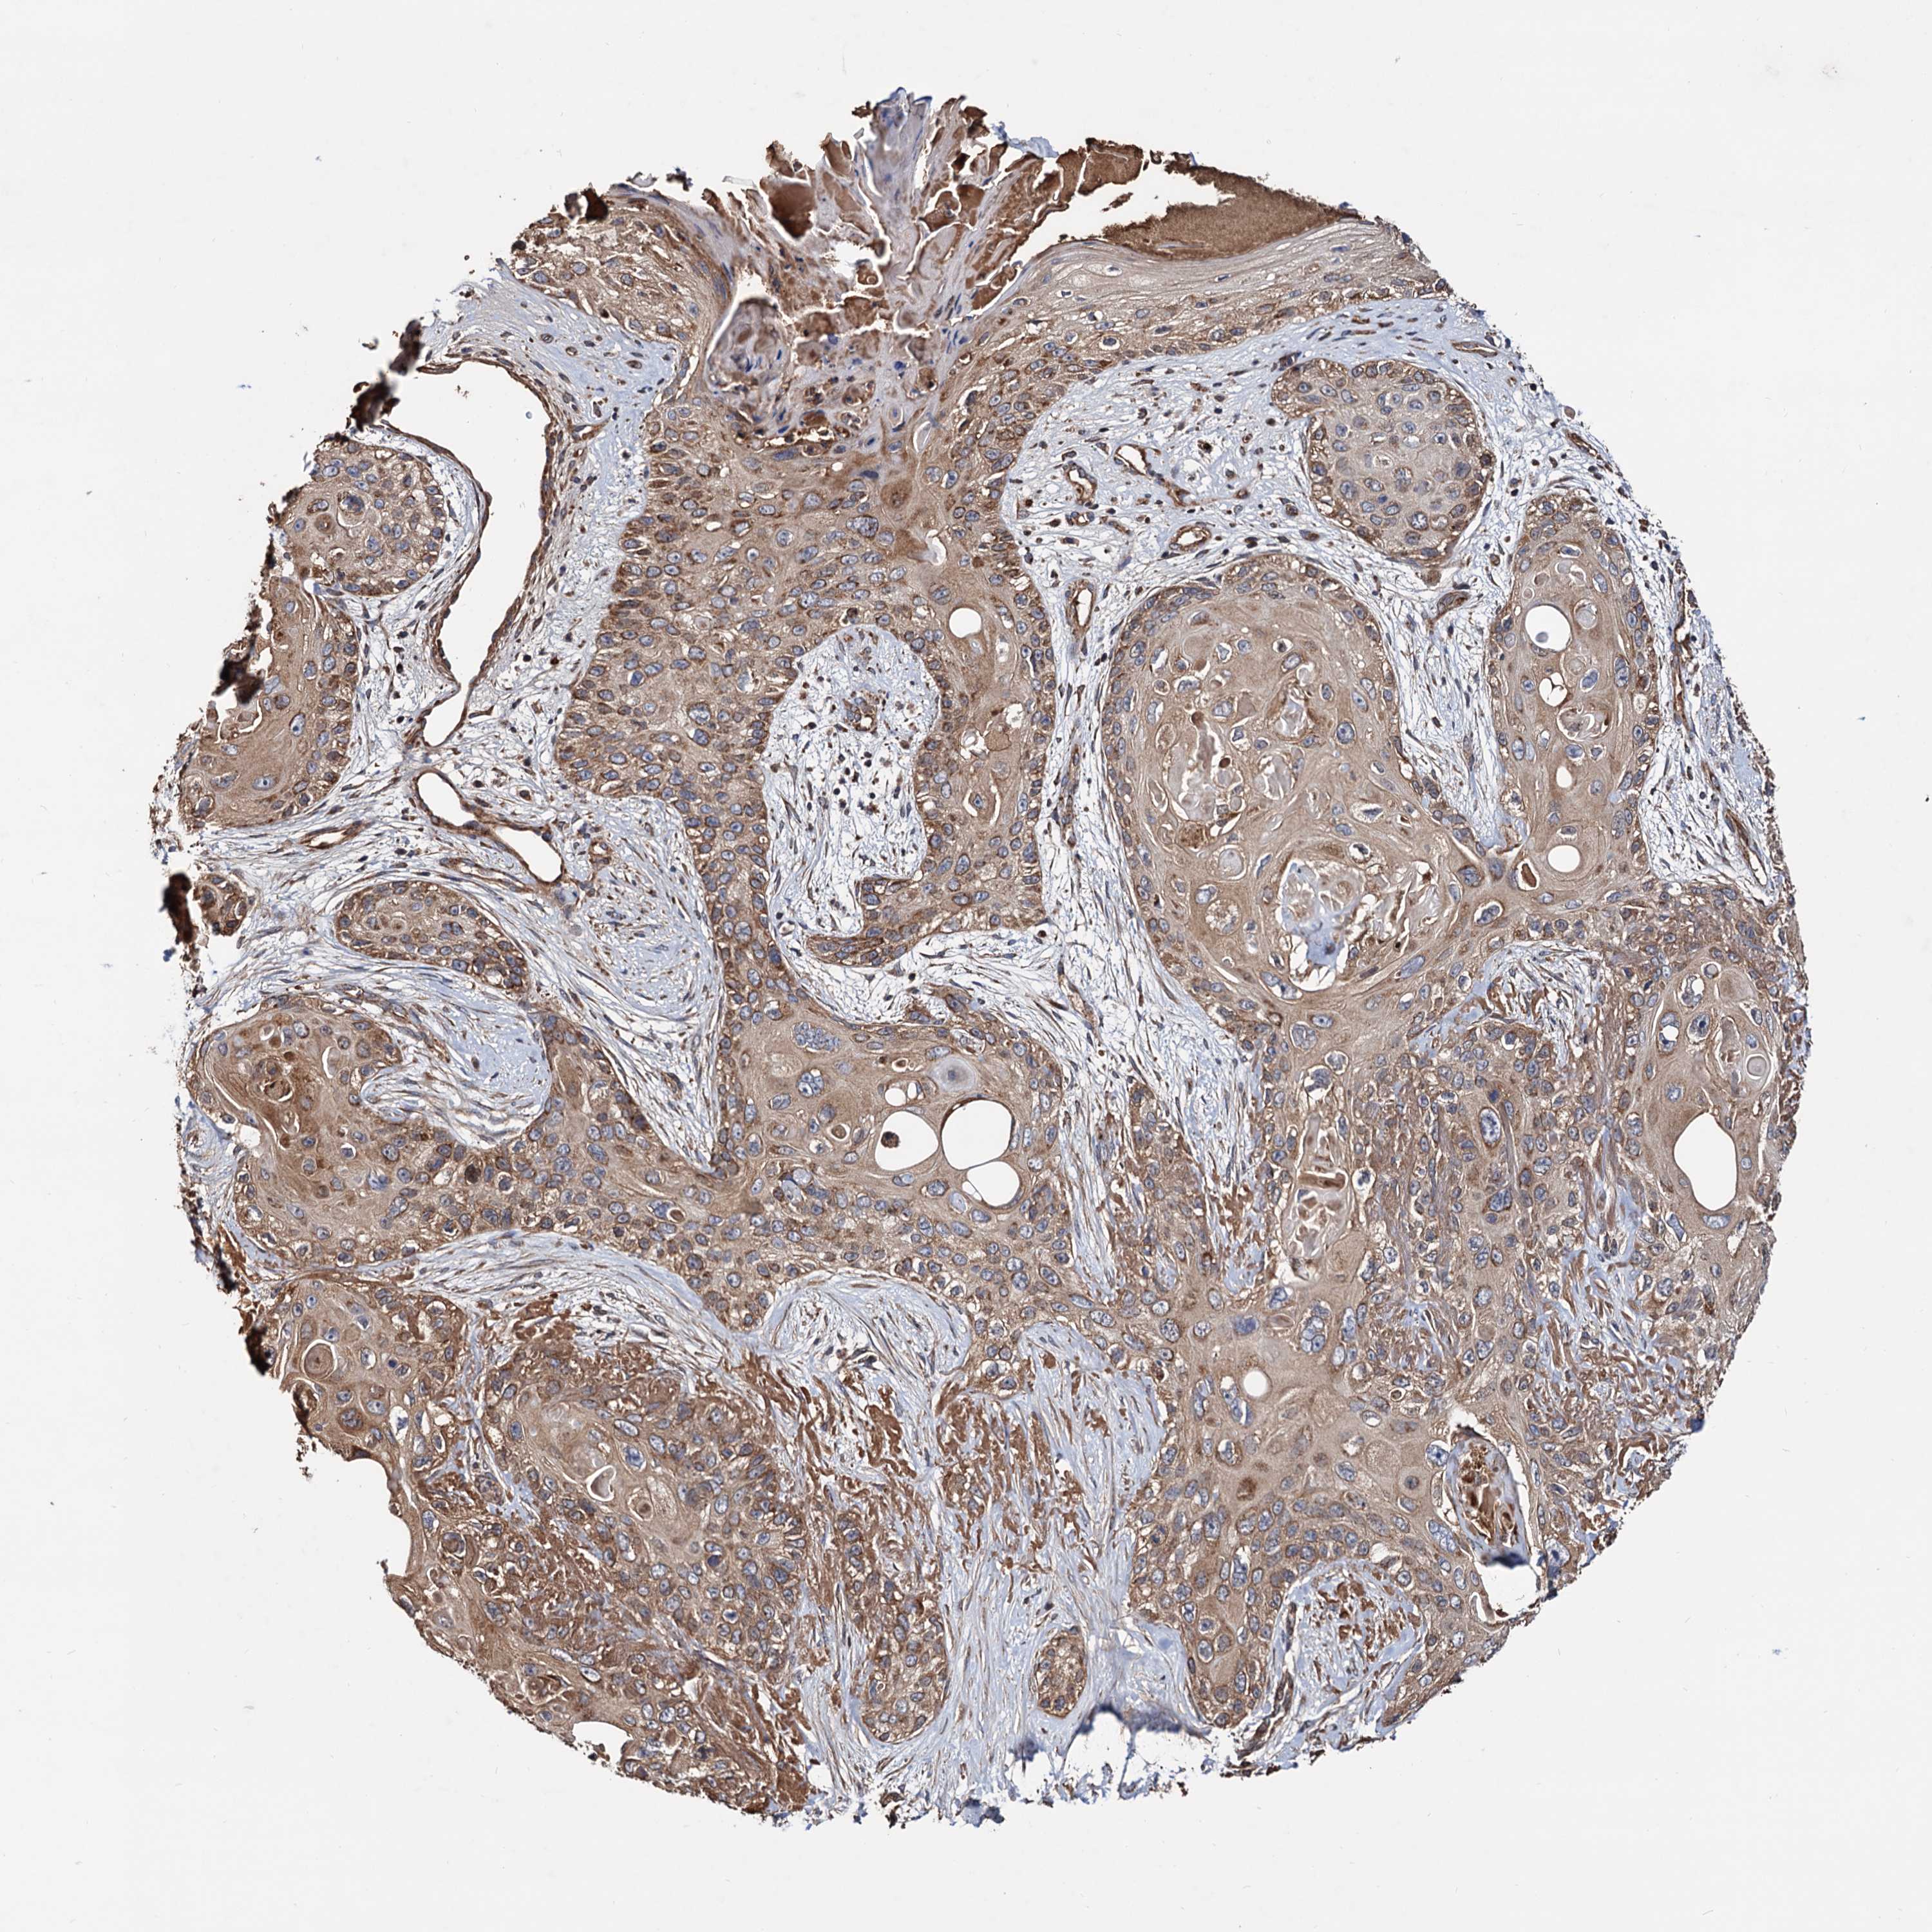

SKIN CANCER - Protein expressioni

A mouse-over function shows sample information and annotation data. Click on an image to view it in a full screen mode. Samples can be filtered based on level of antibody staining by selecting one or several of the following categories: high, medium, low and not detected. The assay and annotation is described here.

Antibody stainingi

Antibody staining in the annotated cell types in the current human tissue is reported as not detected, low, medium, or high, based on conventional immunohistochemistry profiling in selected tissues. This score is based on the combination of the staining intensity and fraction of stained cells.

Each image is clickable and will lead to virtual microscopy that enables deeper exploration of all samples and also displays staining intensity scores, fraction scores and subcellular localization as well as patient and tissue information for each sample.

Antibody HPA039398

Staining

High

Medium

Low

Not detected

Intensity

Strong

Moderate

Weak

Negative

Quantity

>75%

75%-25%

<25%

None

Location

Nuclear

Cytoplasmic/membranous

Cytoplasmic/membranous,nuclear

Basal cell carcinoma

Squamous cell carcinoma, NOS

Squamous cell carcinoma, metastatic, NOS